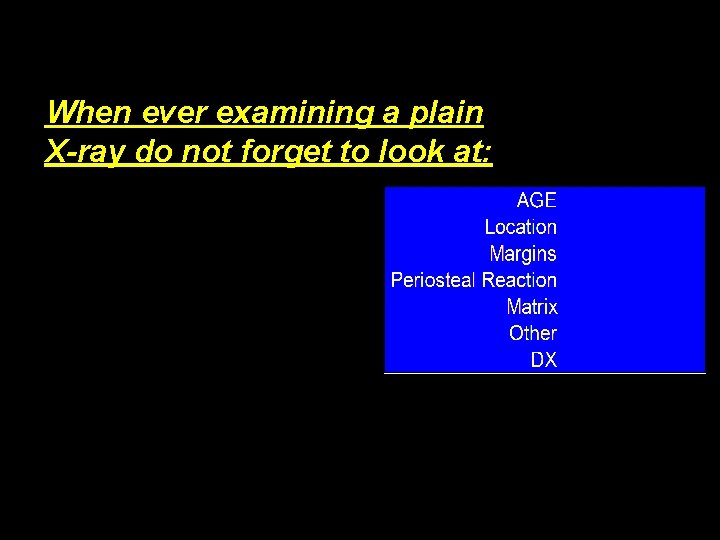

When ever examining a plain X-ray do not forget to look at:

Summary History • Clinical examination • Plain Radiographs are essential for: • Age – Location – Margins – Aggressiveness of process dictates the – response of the bone Isotope scan • CT scan • MRI • Biopsy •